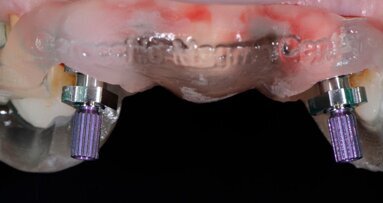

Il protocollo di fresatura biologica BTI a basso numero di giri (50-80 RPM) infine permette di eseguire una chirurgia in condizioni di maggiore sicurezza ambientale per gli operatori in assenza di nebulizzazione senza rischi di surriscaldamento osseo e il particolare design elicoidale, fortemente ritentivo per le particelle ossee che vengono tagliate, consente di ottenere grandi quantità di osso autologo in granuli dalla zona di fresatura (Fig. 7). L’impronta digitale è stata rilevata a fine chirurgia con uno scanner ottico 3Shape Trios (Fig. 8) e contestualmente inviata al laboratorio odontotecnico per la progettazione di una protesi provvisoria di 4 elementi avvitata su impianti utilizzando il programma software 3Shape Dental System (Figg. 9, 10): la protesi provvisoria in PMMA è stata prodotta mediante una stampante dentale 3D ASIGA MAX UV.

Fig. 8 - Scan body per impronta ottica.

Completata la sutura, avvitati 3 Scan Body sui Multi-Im in pochi minuti abbiamo eseguito la scansione digitale intra-orale 3Shape inviandola con un clic al laboratorio odontotecnico il quale ha elaborato, progettato e stampato in 3D la protesi provvisoria in PMMA avvitata con interfaccia estetica su impianti (Fig. 12) da consegnare al paziente tre ore dopo la chirurgia (Fig. 13).